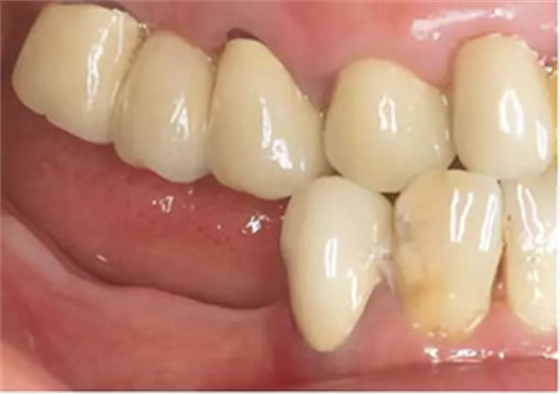

上頜義齒修復(fù)

在2014 年6 月6 日至2014 年11 月24 日期間,為患者做了上頜修復(fù)。由于14 和16 號牙齒的繼發(fā)齲已波及到現(xiàn)有的牙膠充填,所以為這兩顆牙齒做了根管再治療。24 號牙齒在其他醫(yī)生處進(jìn)行了根管治療。為了修復(fù)缺失的15 號牙齒,制作了16 至14 號牙齒的全瓷固定橋;13 號牙齒用全瓷單冠修復(fù);為了修復(fù)缺失的11 號牙齒,用12、21 和22 號牙齒做為基牙,同樣行全瓷固定橋修復(fù)。其余的牙齒用全瓷單冠修復(fù)。然后用長期臨時(shí)義齒修復(fù)下頜。